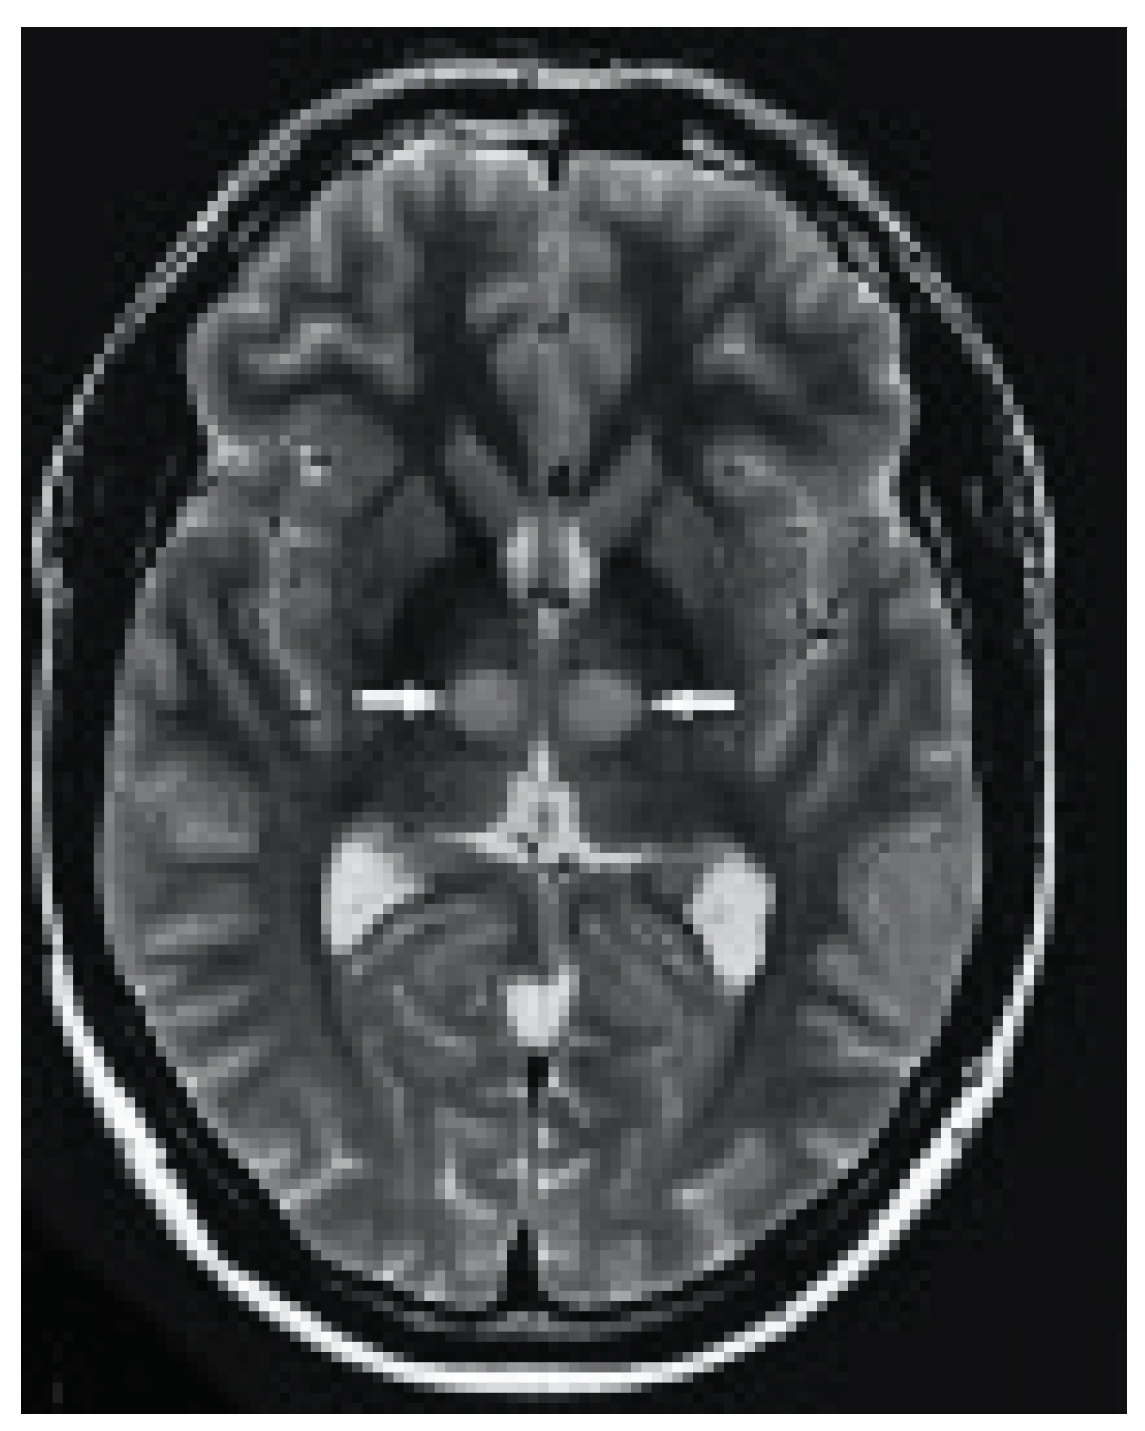

Radiological Investigations: